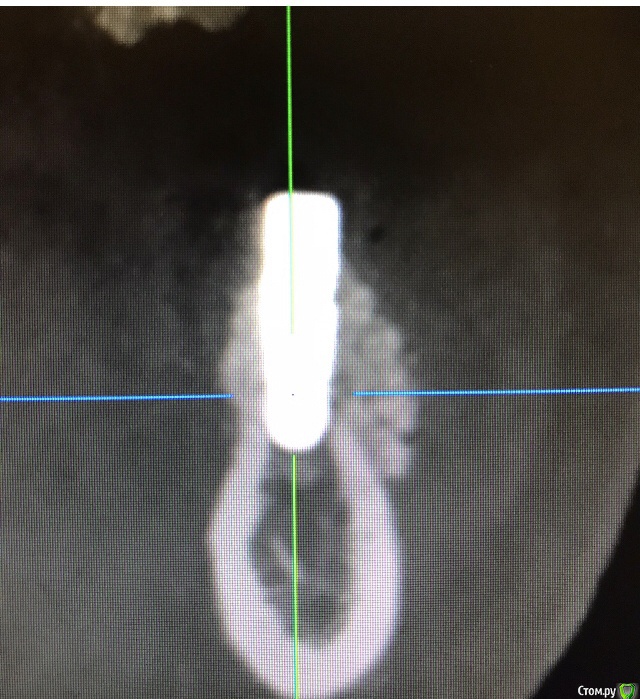

колесников Опубликовано 29 сентября, 2019 Автор Поделиться Опубликовано 29 сентября, 2019 (изменено) Старая чужая работа в плане хирургии и свежая ортопедия ,пациентка мнительная и знакомая учередителей и хирург и ортопед их старые знакомые и ещё цементная фиксация. Нужно было сделать минимально инвазивно,без переделки коронок,без периода «без зубов» и сильно не умничать. Были жалобы на застревание пищи ,на тянущие ощущения и прочий дискомфорт. Десна выглядела тонкой,просвечивались абатменты,но к счастью без воспаления,это фрезерованные Нобеля. У шеек десна так и осталась тонкой ,но ушло напряжение. По снимку я показал какой был гребень и какой стал валик,валик ниже вершины гребня,ниже шеек имплантов. Отслаивать тоннельно при стоящих имплантат в верх-очень рисковано ,можно потерять герметизм и все стухнет. Потому,пусть тонка но прикреплённая слизистая остаётся там где она есть,амниже располагается костный валик,теперь нет напряжения в мягких тканях на вершине гребня,они будут постепенно созревать под воздействием ирригатора. Обычно после я делаю стрип пластику,но врядли мне это дадут сделать. Фото через неделю сделаю Вот вчера подобное делал. Тоже Нобеля и тоже снимать нельзя ,осложнено положением имплантов в 45градусов и импланты на 1/3 Вестибулярно не в кости. На выглядит более менее,но это все мягкие ткани Изменено 29 сентября, 2019 пользователем колесников Ссылка на комментарий

колесников Опубликовано 25 июня, 2020 Автор Поделиться Опубликовано 25 июня, 2020 Подтянуть первую ко второй или вторую к первой?). Аугментат созрел и интегрирован-в этом суть контрольного снимка,снимок «до» даёт понимание по объёму и форме дефекта. Вот так выглядит свежий графт (1),вот так созревший (2). И поперечные срезы. Все это уже давно запротезировано. Ссылка на комментарий